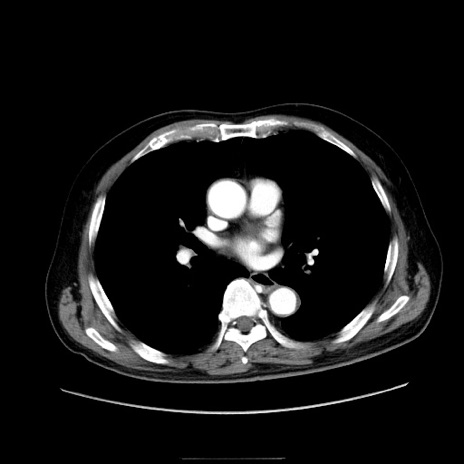

症例30(横断像)

【症例】80歳代男性

【主訴】臍周囲痛

【現病歴】約6時間前から臍下部痛が出現。次第に腹部膨隆・背部痛も生じてきたため来院。背部痛の場所は変化しない。

【身体所見】意識清明、BT 36.3℃、BP  131/87mmHg、P 87bpm、SpO2 100%(RA)、臍周囲自発痛・圧痛あり、反跳痛なし、自発痛部位に一致して板状硬あり、腹部膨隆、腸雑音減弱、CVA tenderness両側陰性。